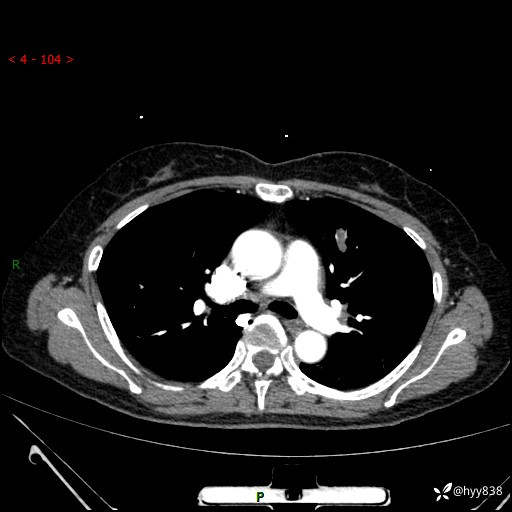

54岁/女,发现肺占位1天。观其形态和强化,术前我信心十足,术后我---结果公布~

【患者信息】:54岁/女

【主诉】:发现肺占位1天

【现病史及既往史】:患者2023.10.23体检发现肺占位:,2023.10.23当地区中心卫生院胸腹部CT:1.左肺上叶结节,考虑为占位可能;2.肝脏小囊肿灶;3.子宫左侧附件区畸胎瘤;无咳嗽咳痰,无恶心呕吐,无发热,无胸闷胸痛等不适;现患者为求进一步诊治来我院,门诊以“肺占位”收入我科。 患者自起病以来,精神饮食睡眠一般,大小便正常,体力体重无明显下降。

【检查】:胸部CT增强(外院平扫)